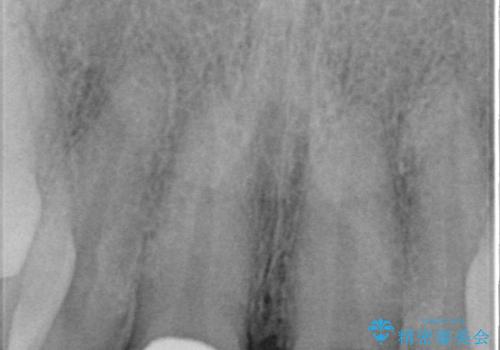

- 前歯のすきっ歯を気にして来院された患者様です。

矯正かオールセラミックか、治療の選択がありましたが、ご年齢や色の濃い点を考慮してオールセラミッククラウンにて補綴することとしました。